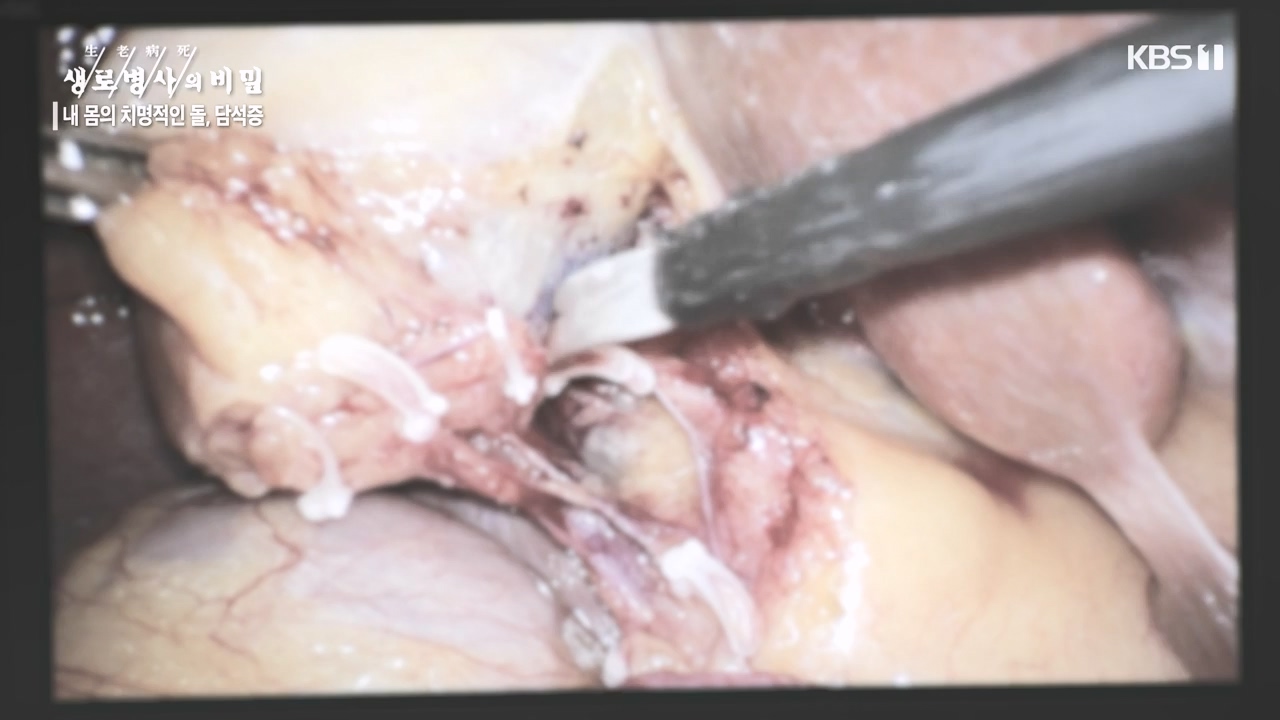

[박은철 기자] 담석증은 지방 소화를 돕는 담낭(쓸개)에 담즙이 굳어서 돌처럼 덩어리가 생기는 질환이다. 주로 쓸개주머니라 불리는 담낭 안이나...

다양한 합병증을 유발하는 몸속 시한폭탄, 담석증

내 몸의 치명적인 돌 담석증